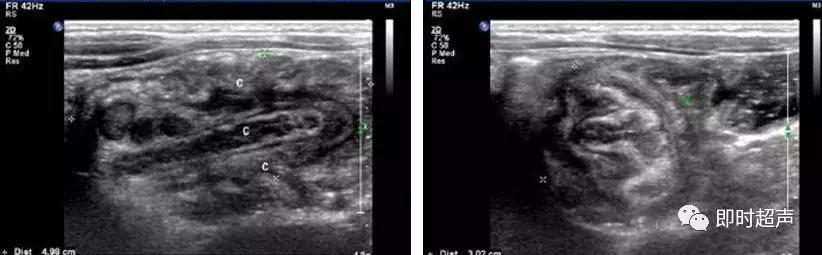

超声表现

低回声团:短轴 靶环征

长轴 套筒征

偏心 阑尾、息肉等

肠套叠超声表现

短轴切面同心圆征

长轴切面套筒征、短轴切面同心圆征